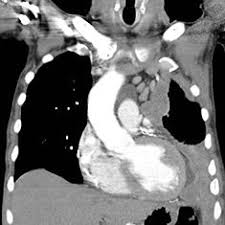

The mesothelium of the chest is known as the pleura. The mesothelium of the abdomen is called the peritoneum. The mesothelium of the pericardial cavity, which is the space around the heart, is called the pericardium.

Mesothelioma is a cancer that attacks any of these mesothelial regions.